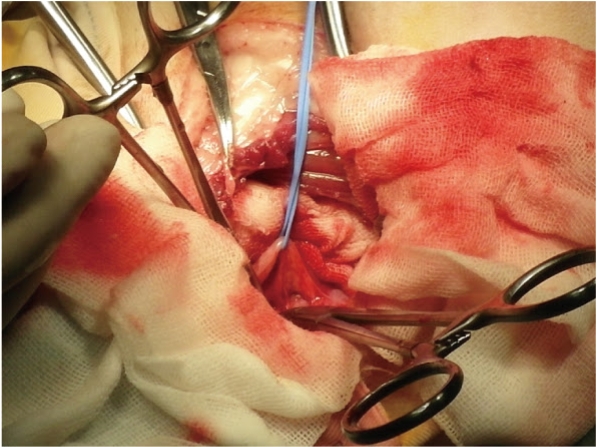

術中動脈導管的破裂是PDA手術最嚴重的併發症。在正常狀況下,動脈導管在出生後幾天內會自然的封閉,唯有動脈導管異常的個體,常因為動脈壁過於脆弱導致術中破裂;在過去主刀的八個PDA開胸手術中,出現過一次導管破裂大出血;一位六公斤的吉娃娃患者,組織結構分級為grade 6,在剝離PDA瞬間爆血,不到三秒鐘的時間,血液已瀰漫整個胸腔…此刻,只能快速以止血钳止住出血點,馬上輸血150CC,那偌大的心臟從一秒搏動二百下,下降到每秒十五下…眼看就要失去她了…在強力的輸血下,輸入的血量再度水及時地充盈左心,收縮壓由監控不到,再次站上130Mmhg⋯

在經歷了一次生離與死別,慶幸在術前有備了血液;在這種狀態下,已經無法用標準模式去紮掉動脈導管;我選擇的是另一種手術通路⋯Jackson approach:先從PDA的右側進入,以左手食指剝離下行主動脈下的肌膜,藉以繞道主動脈下方,PDA左邊也用相同方法,如此即可避開脆弱的動脈導管,順利完成ligation

【圖四】 假若不慎弄破動脈導管,建議,先以止血鉗夾住出血點,

必要時,緊急輸血;至於出血的地方,以血管夾或帶有補片的不可吸收線材與以縫合